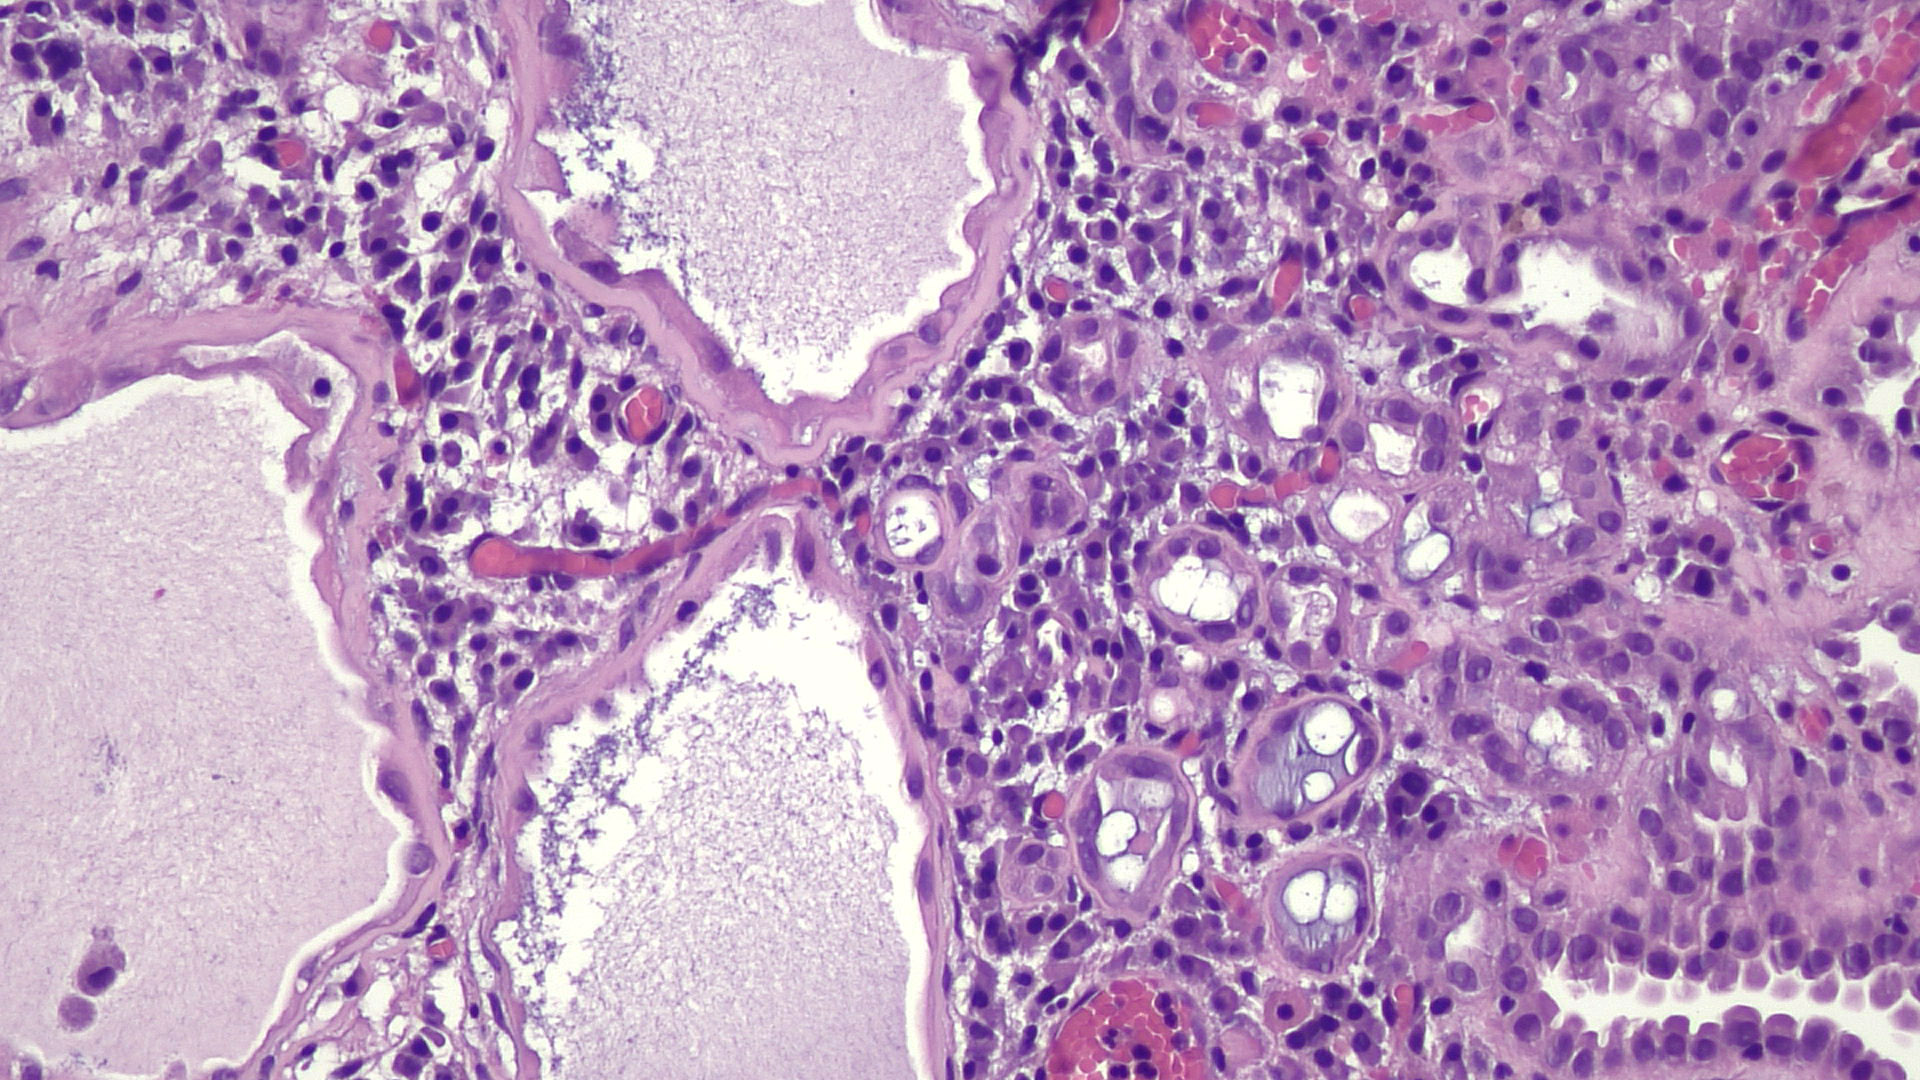

- Tubules lined by simple cuboidal, flattened or hobnail cells, forming an exophytic papillary or endophytic lesion (Urology 2016;95:29)

- Associated acute and chronic inflammation and edema in the stroma; lack of desmoplastic reaction

- Hyaline rim surrounds the tubules (PAS positive thickened basement membrane) (Adv Anat Pathol 2019;26:171)

- Scant cytoplasm, finely granular uniform chromatin; usually inconspicuous nucleoli (Ann Diagn Pathol 2019;38:11)

- Only occasionally solid areas, rare clear cells, blue mucin within the tubules present

- Sometimes atrophic tubules filled with eosinophilic colloid-like material mimicking thyroid follicles and mesonephric hyperplasia

Microscopic (histologic) images